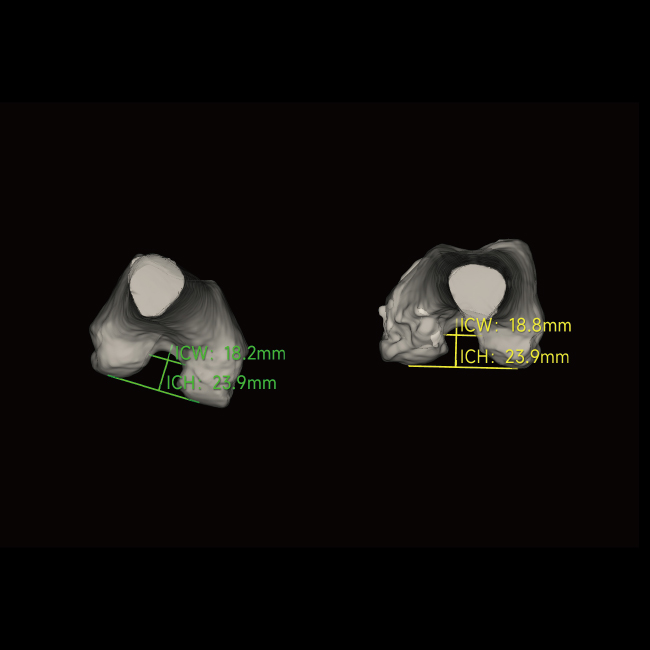

「 全 」全球首台三维骨关节与AI测量负重锥束CT

临床图像